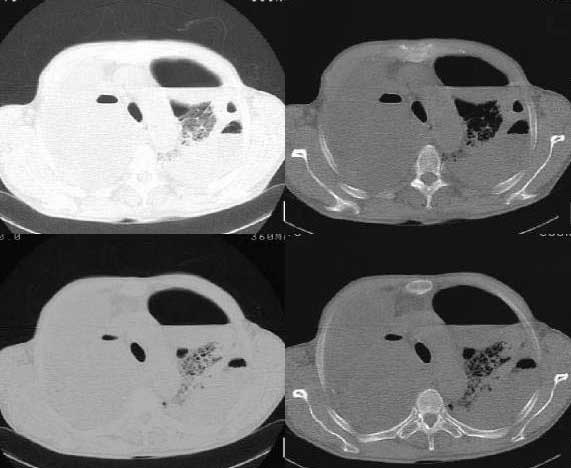

以下是引用woaixct在2006-6-23 12:15:00的发言:[br]第一张胸片示:右肺上叶为大片致密影占据,左肺上见大片致影及空洞性病灶并有液平;[br]第二张胸片示:左肺上叶致密影及空洞性病灶基本吸收,而右肺上叶之病灶有少许吸收改变;[br]ct片示:右上叶大片软组织密度,右肺门区至右肺上叶见巨大软组织块,内见支气管充气征,上纵隔右移,主气管及上叶支气受压变扁,中间支气管狭窄,左肺上叶空洞性病灶并有液平,左肺上叶尖后段见大片致密影,结合2张胸片考虑,ct片是4月份所摄,而不是6月份的片子;[br]结合2张胸片及ct片考虑:[br] 1.右中央型肺癌伴右肺上叶不张;[br] 2.左肺上叶尖后段炎性变及左肺脓肿;[br]第2张胸片提示:经过一个多月的不规则抗炎治疗,左肺上叶病灶及右肺上叶不张病灶基本吸收,而右肺占位无明显变化。

以下是引用jiangjing在2006-6-23 21:21:00的发言:[br]个人考虑还是两肺感染性病变可能大,主支气管及叶支气管是通畅的,并可见支气管气相;ct提示病变是以肺叶分布的,密度相对均匀;胸片可见有叶间裂下坠征,是不是考虑克雷伯杆菌感染可能.病人前后两张片比较病变是增多[应该考虑混合感染可能性大,右肺癌待排建议查痰及穿刺检查]